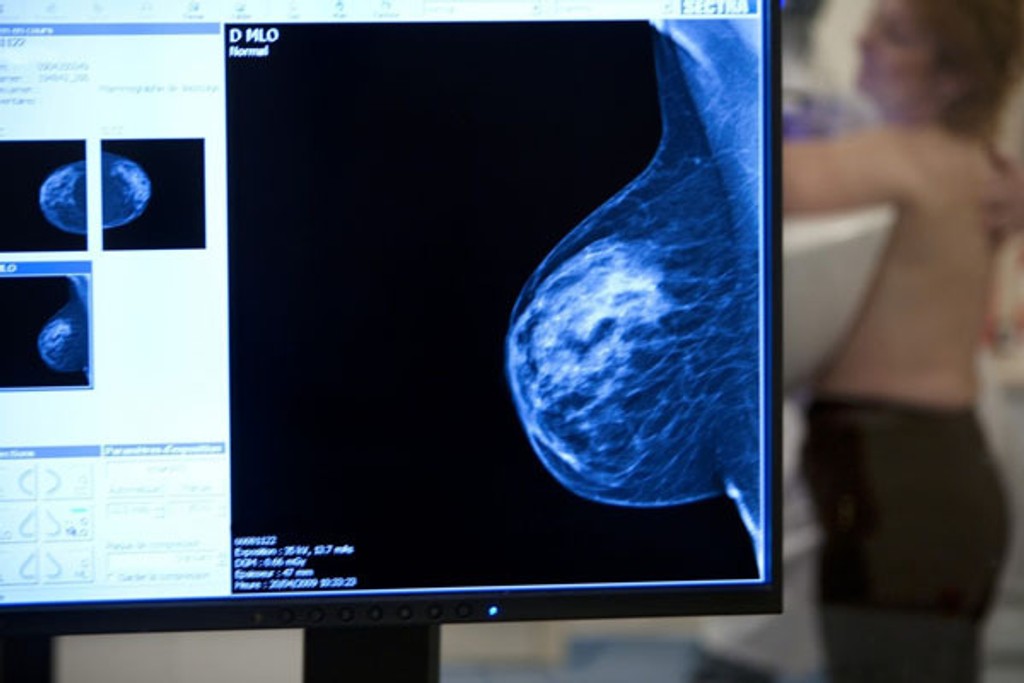

Štúdia spochybnila význam mamografického vyšetrenia prsníka

Vyšetrenie prsníka

Zdroj: Profimedia.cz

Rozsiahla kanadská štúdia spochybnila význam preventívneho vyšetrovanie mliečnej žľazy u žien. Mamografické vyšetrenie síce zachytí nádor včas, avšak podľa štúdie je úmrtnosť na rakovinu prsníka u žien, ktoré screening prekonali, rovnaká ako u tých, ktoré ho nemali. Výskum trval zhruba 25 rokov a zapojilo sa do neho 90 -tisíc žien.

Štúdia, ktorú minulý týždeň zverejnil časopis The British Medical Journal, náhodným spôsobom vyberala Kanaďanky, ktoré potom pravidelne podstupovali mamografické vyšetrenie, vyšetrenie prsníka v ordinácii, alebo si ich vykonávali samy.

Výskumníci chceli zistiť, či je výhoda v tom, keď sa rakovina prsníka zistí vo fáze, kedy je nádor tak malý, že sa nedá ani nahmatať. Došli ale k zápornej odpovedi.